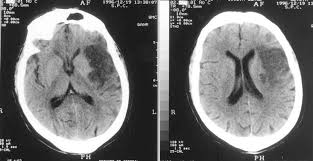

TDM (Scanner) Cérébral: L’Ischémie apparait comme une hypodensité spontannée (noire ou sombre) dans le territoire vasculaire atteint

- AVCI sylvien superficiel:

On peut également avoir des signes indirects avant 48h au scanner (effacement des sillons corticaux,trop belle artère sylvienne):

TDM (Scanner) Cérébral: L’Hémorragie apparait comme une hyperdensité spontannée (blanc) dans le parenchyme ou les ventricules

- Hémorragie cérébro-méningée avec inondation ventriculaire: